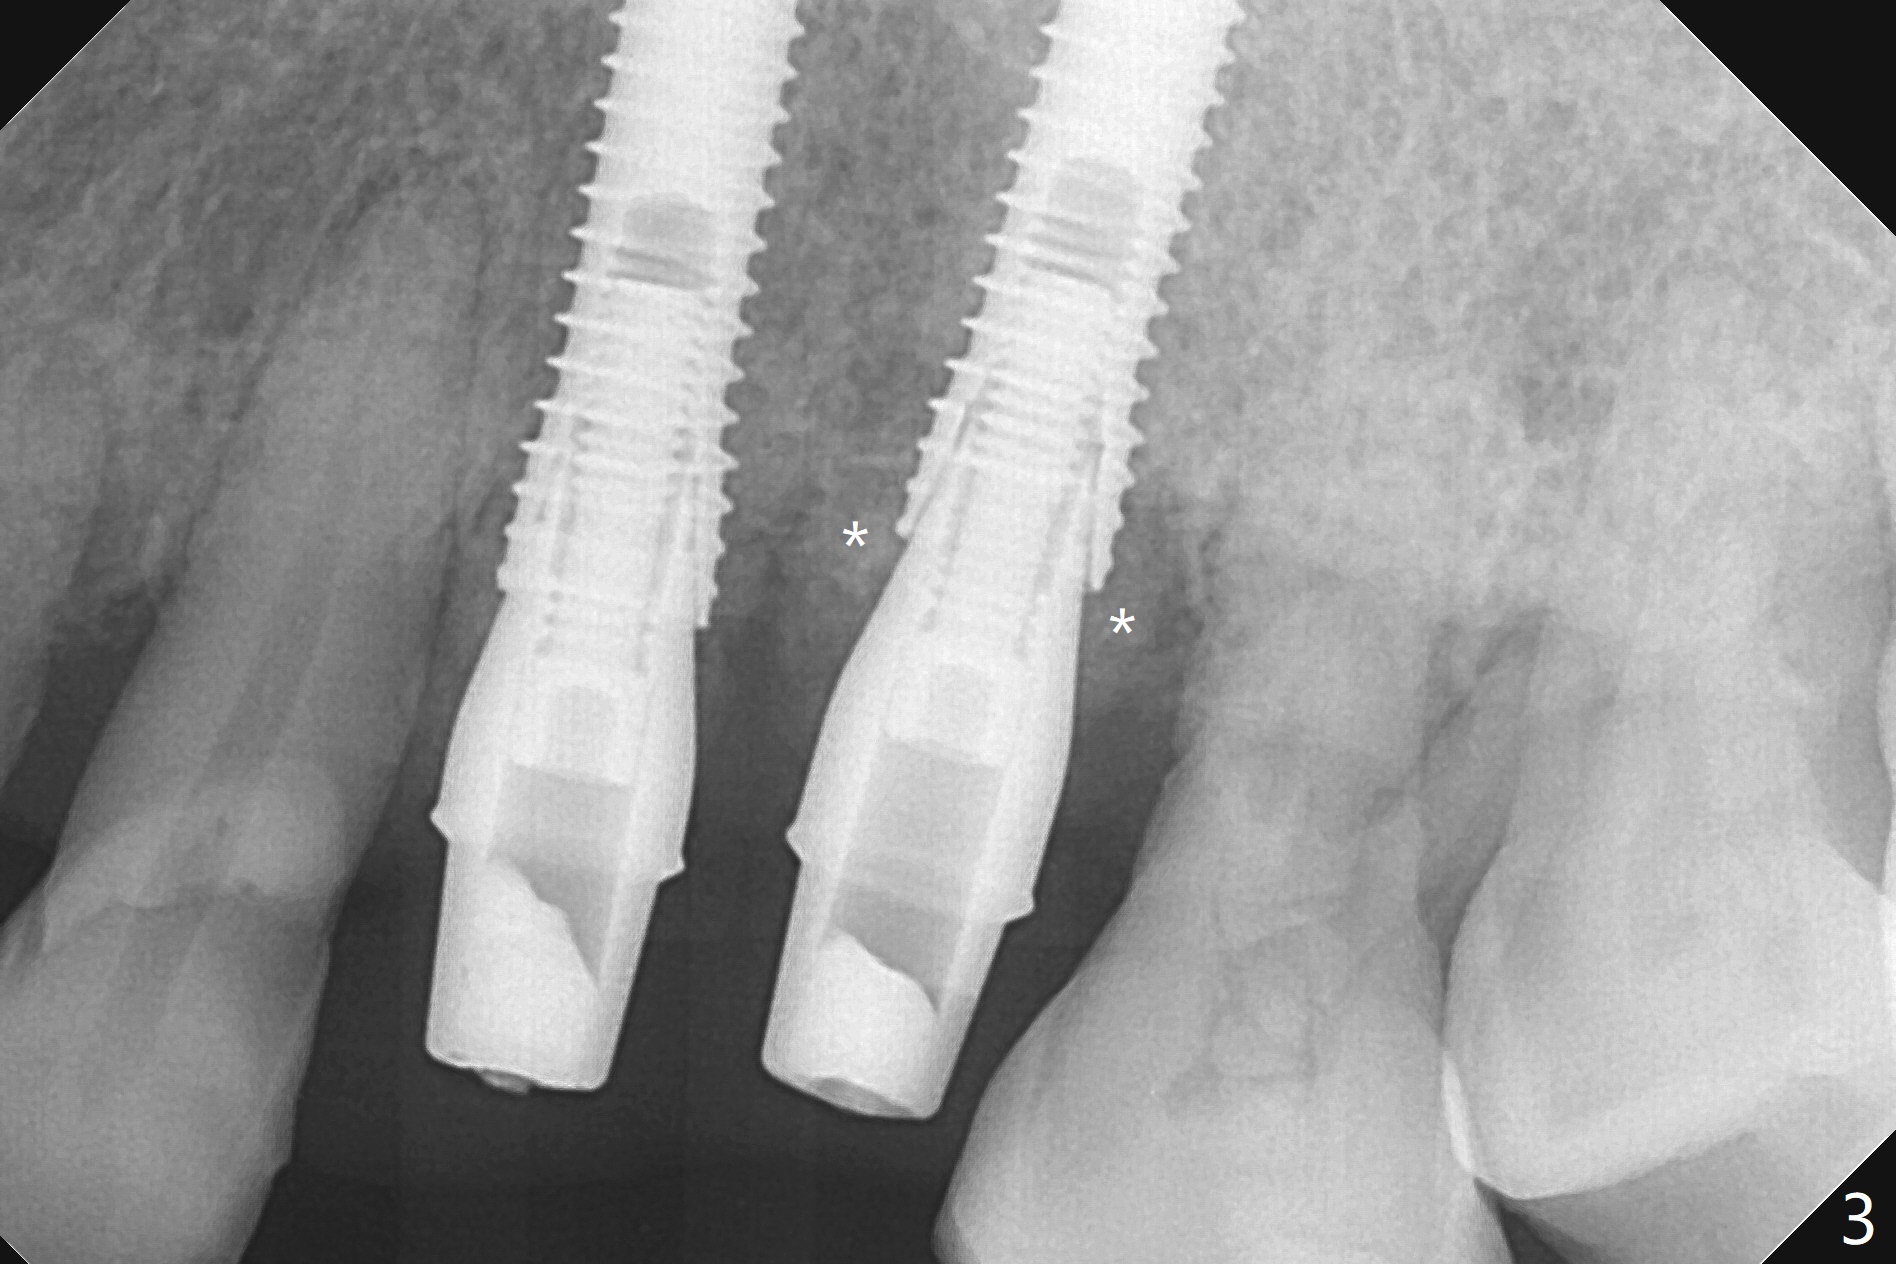

A 66-year-old woman returns to office requesting implant placement at #12 and 13 at an appointment supposed for #5 impression. Depth of osteotomy is 20 mm (gingival level, Fig.1 ( 2mm)). After correction of trajectory at #12 and 3 mm drill for 16 mm at the sites, two of 3.8x16 mm implant are placed with insertion torques of 35 and 15 Ncm, respectively (Fig.2). Before and after change into shorter abutments (4.5x4(4) and (5)), Vera Graft is placed (Fig.3 *). To increase stability, either increase the diameter (4 (Fig.4 at #5) or 4.5 mm instead of 3.8) or length of the implants (red dashed line: sinus floor). Or use dummy implants. The allograft appears to have been incorporated into the host bone nearly 4 months postop (Fig.5). The abutment of the isolate implant at #5 becomes loose twice (Fig.4). To reduce the chance of abutment loosening at #12 and 13, can you make splinted crowns? If the two separate crowns have been fabricated, can you make a slot (with light undercut) in the proximal area of each crown (Fig.6 (occlusal view): S) in addition to access hole (A)? After cementation, composite will be placed in the slots (lock) so that the crowns will not rotate and become loose.